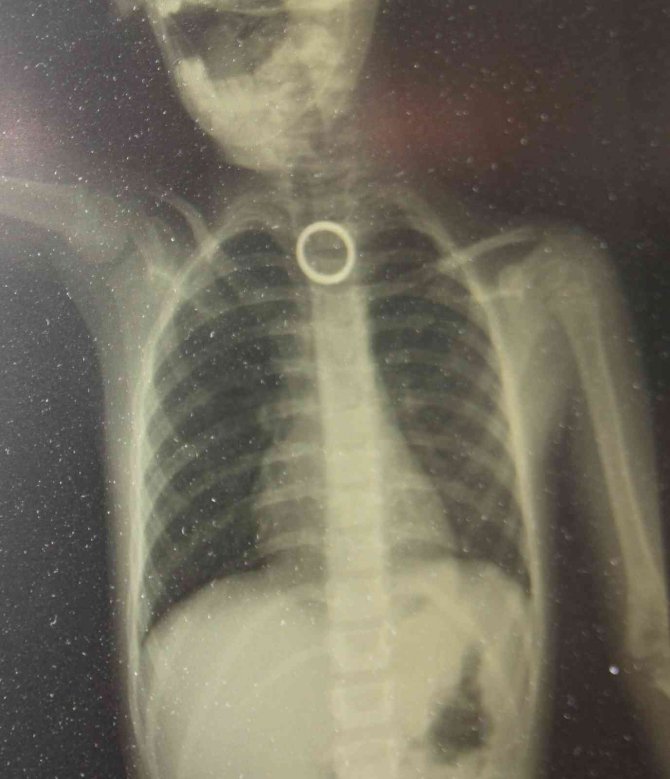

3 yaşındaki çocuğun yutması sonucu yemek borusuna sıkışan yüzük, yapılan cerrahi operasyonla çıkartıldı.

Elazığ'da 3 yaşındaki çocuğun yutması sonucu yemek borusuna sıkışan yüzük, yapılan cerrahi operasyonla çıkartıldı.

Elazığ'da evde oyun oynayan 3 yaşındaki çocuk, yakınında bulunan yüzüğü yuttu. Durumu fark eden ebeveynler çocuğu hemen Fırat Üniversitesi Hastanesine getirerek Çocuk Gastroenteroloji Ana Bilim Dalı Başkanı Prof. Dr. Yaşar Doğan'a gösterdi. Burada yapılan tetkiklerde yutulan yüzüğün yemek borusu birinci darlık kısmında takılı kaldığı görüldü. Hemen Çocuk Endoskopi Ünitesine alınan 3 yaşındaki çocuğun boğazındaki yüzük yapılan endoskopik yöntemle çıkartıldı. Sağlık durumu iyi olan çocuk taburcu edilirken, uyarılarda bulunan Çocuk Gastroenteroloji Ana Bilim Dalı Başkanı Yaşar Doğan, bu tür vakaların meydana gelmemesi için ailelerin, çocukların etrafından bulunan yabancı cisimleri uzaklaştırmaları gerektiğini belirtti.

Hastanın 3 yaşında olduğunu belirten Çocuk Gastroenteroloji Ana Bilim Dalı Başkanı Prof. Dr. Yaşar Doğan, "Bu hastamız akşam saatlerinde boğazına yabancı cisim yutma yakınmasıyla ailesi tarafından hastanemize getirildi. Yaptığımız incelemeler neticesinde özellikle yemek borusunun birinci darlık kısmında yüzüğü benzer bir yabancı cisim gördük. İlk geldiğinde hasta yeni beslendiğinden dolayı endoskopi için açlık süresi bekletildi. Ondan sonra gerekli olan endoskopi işlem yapılarak oradaki yabancı cisim çıkartıldı. Çıkarma işlemi başarılı bir şekilde yapıldıktan sonra aile 2 saatlik gözlemden sonra evine gönderildi. Şu anda herhangi bir sıkıntısı yok. Bu gibi vakalar bize çok fazla gelmektedir. Özellikle mevsimler değişkenlik dönemlerinde evlerde temizliğin yapıldığı dönemlerde ailenin çocuğu rahatlıkla gözlemleyemediği dönemlerde çocuklar etrafında buldukları her yabancı cismi ağızlarına götürme eylemindeler. Özellikle yabancı cismin nefes borusu veya akciğer kaçması ölümcül nedenlere yol açabilir ama yemek borusu veya sindirim sistemine kaçmış olan yabancı cisimler erken getirildiği zaman endoskopik yöntemlerle çıkarabilmekteyiz. Bu tür vakaların meydana gelmemesi için ailelerin tam bilinç seviyesi yerine gelmemiş çocukların etrafında yutabilecekleri bütün yabancı cisimleri uzaklaştırması gerekir. Yoksa çok kötü sonuçlarla karşılaşabiliriz" dedi.